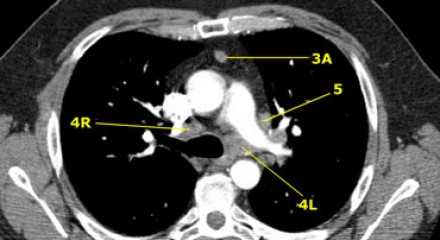

Лимфатические узлы 3 группы не примыкают к трахее в отличии от лимфатических узлов 2 группы. Они подразделюятся на: 3А кпереди от сосудов 3Р позади пищевода/превертебрально Они не доступны при медиастиноскопии. 3Р группа может быть доступна при чреспищеводной эхокардиографии.

На изображении слева 3А узел в преваскулярном пространстве. Обратите внимание так же на ниже расположенные паратрахеальные узлы справа относящиеся к 4R группе.

4L. Левые нижние паратрахеальные лимфатические узлы

4L узлы расположенные слева от левой стенки трахеи, между горизонтальными линиями проведенными касательно верхней стенке дуги аорты и линией проходящей через левый главный бронх на уровне верхнего края верхнедолевого бронха. Они включают паратрахеальные узлы расположенные кнутри от артериальной связки.

Узлы 5 группы (аортопульмонального окна) расположены кнаружи от артериальной связки.

На левом изображении над уровнем легочного ствола представлены нижние паратрахеальные узлы слева и справа, так же здесь представлены узлы 3 и 5 групп.

Изображение слева выше уровня карины. Слева от трахеи 4L узлы. Обратите внимание что они расположены между легочным стволом и аортой, но не в аортопульмональном окне, потому что они лежат медиальнее артериальной связки. Лимфатические узлы латеральнее легочного ствола относятся к 5 группе.

- 5. Субаортальные лимфатические узлы

- Субаортальное или аортопульмональное окно расположено кнаружи от артериальной связки и проксимальнее первой ветви левой легочной артерии и лежит в пределах медиастинальной плевры.